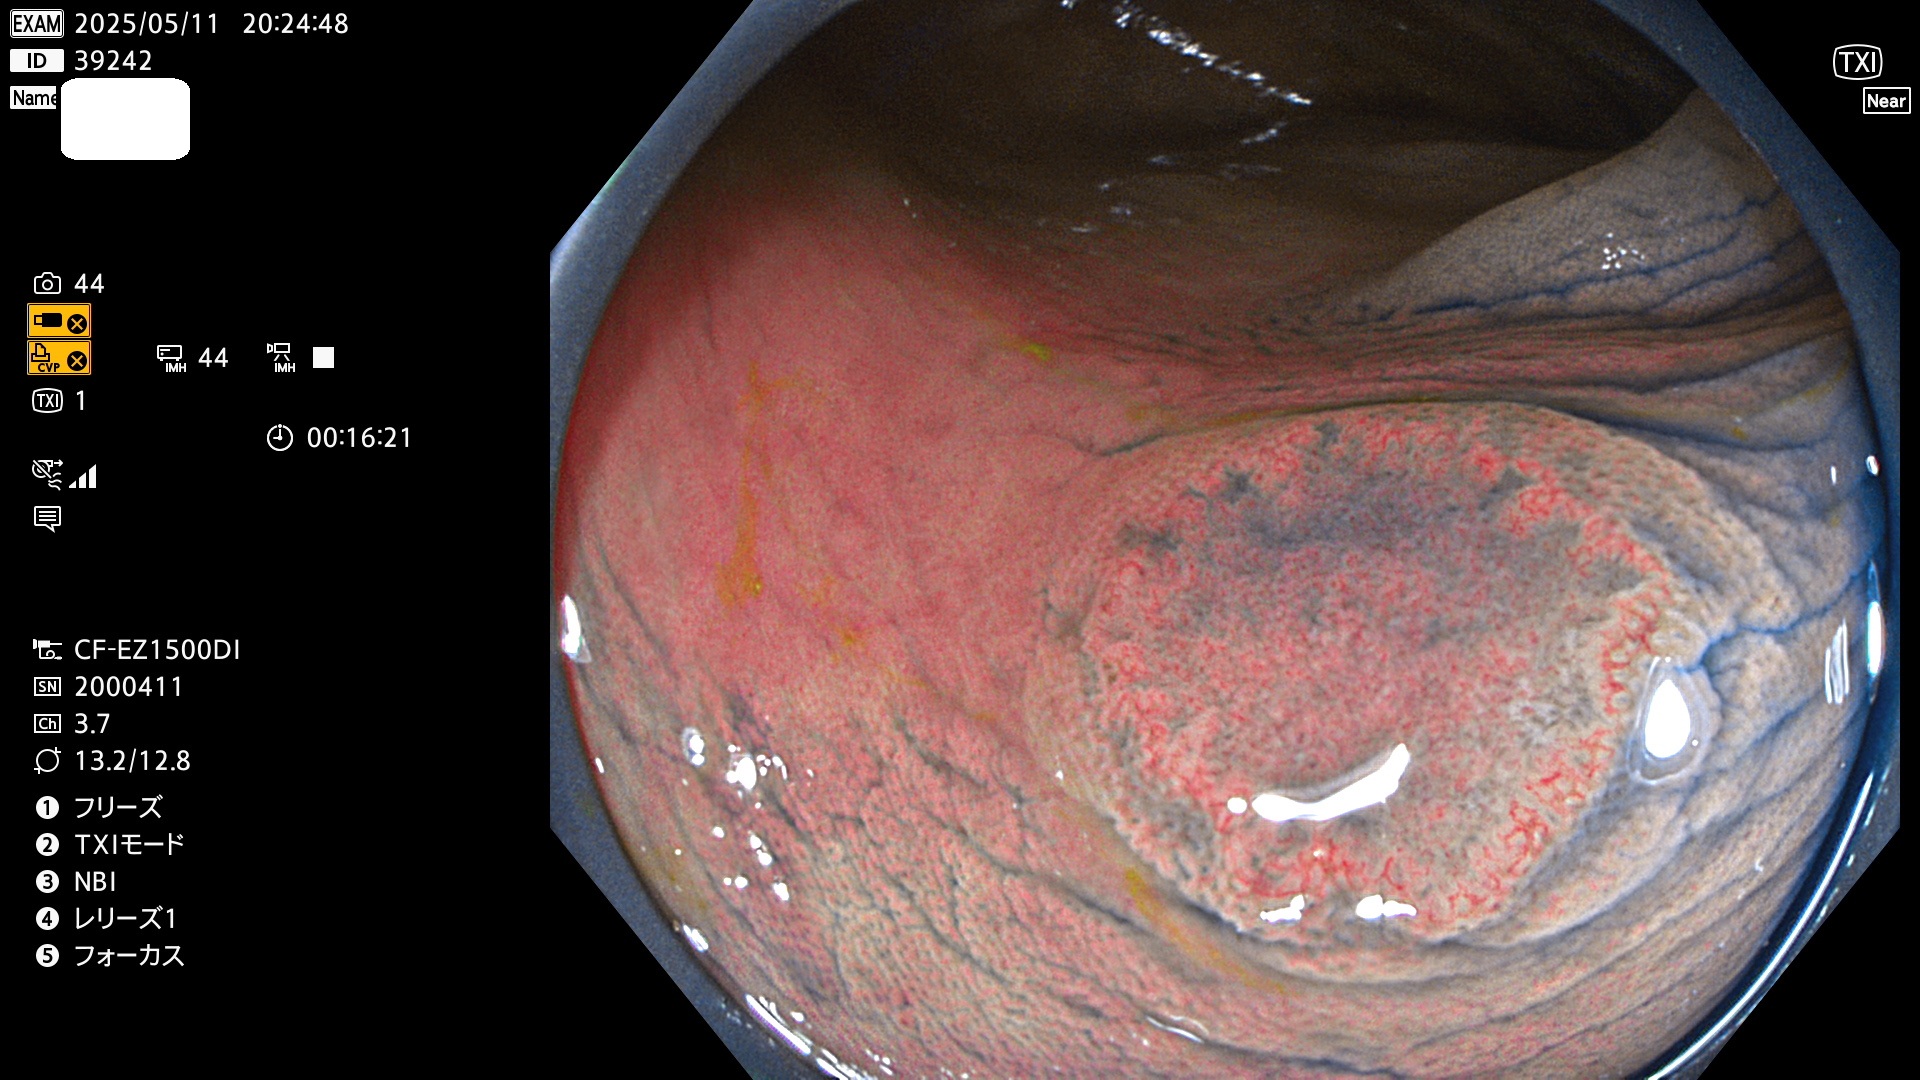

完全に平坦な物をUb、陥凹している物をUcと呼びます。Ubは認識が困難で、Ucはびらん(炎症)と紛らわしいために見落とされやすく、「内視鏡後・大腸癌」の原因になります。

抽出の対象期間 2025年5月8日〜5月11日の4日間(48件の検査)14個 (14/48=29%)